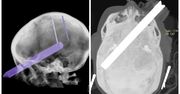

Stłuczenie mózgu to uraz, który powstaje w wyniku silnego przyspieszenia i hamowania głowy. To skutek ruchu mózgu w obrębie czaszki. Uszkodzenie ma charakter zamknięty, co znaczy, że nie doszło do przerwania ciągłości tkanek otaczających mózgowie. Choć nie wygląda groźnie, może mieć poważne konsekwencje. Jakie są niepokojące objawy? Na czym polega leczenie?